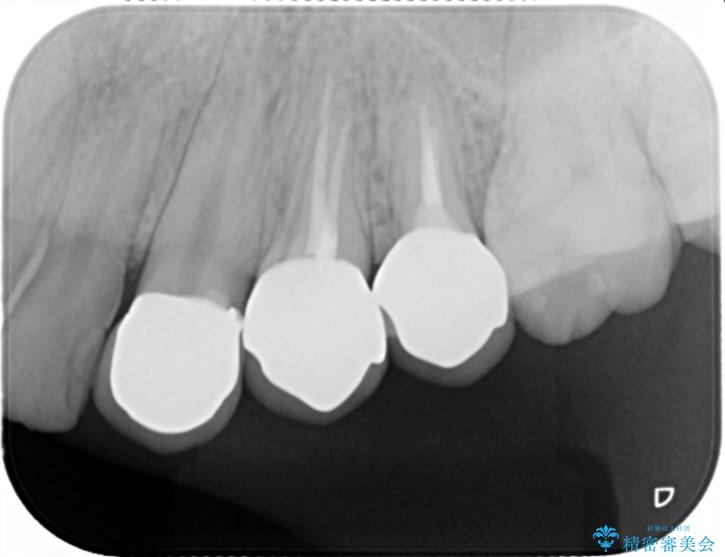

- 歯ぐきの腫れや、歯の内部が黒く見えることからの虫歯の治療を求めて来院されました。

虫歯が大きかったことから、神経の温存はできたものの歯ぐきよりも深い虫歯の問題を解決するため部分矯正治療を併用したセラミック治療を行うこととしました。

当初、歯ぐきよりも深い虫歯のぞんざいや、歯のポジションに問題がありましたがマルチブラケットを用いた部分矯正を行うことで適切な位置へと歯を移動させ、歯周環境を整えたセラミック治療を行うことができました。